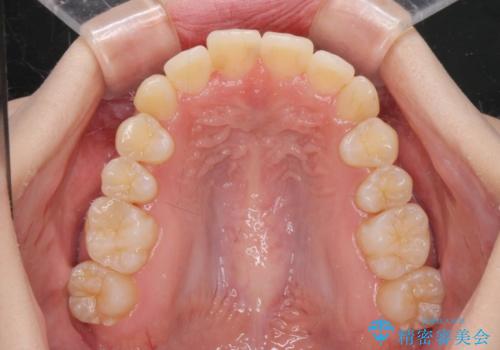

前歯のがたつきをマウスピース矯正できれいに!

- 目立つ前歯のがたつきを改善したい、と矯正治療を希望され来院されました。

マウスピース矯正システムインビザラインを用いて複数のシミュレーションを検討し、最適なゴールへ至る矯正治療を計画します。

今回の治療ではシミュレーションでしっかりと検討した結果、下顎は前歯を1本抜去し仕上げる治療計画としました。